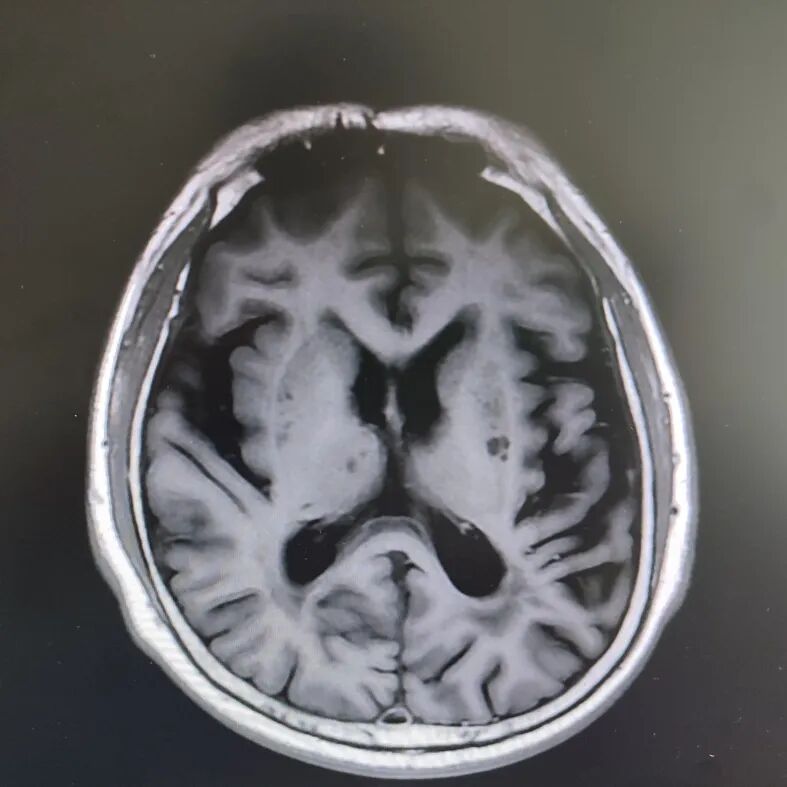

病房里還有另一位患者,來的時候情況更讓人揪心:反應遲鈍,表情呆滯,行動緩慢。頭顱核磁顯示腦萎縮明顯,但查體發(fā)現肌張力、計算力、記憶力、定向力均正常,不符合典型血管性癡呆或阿爾茨海默病表現。

患者頭部磁共振影像

憑著多年診治疑難雜癥的豐富經驗,趙主任敏銳地意識到這“癡呆”可能是假象,背后另有隱情。他果斷建議進一步做特殊感染篩查。果然,檢查證實這位患者同樣是感染了蒼白密螺旋體!經過精準的抗感染治療,奇跡發(fā)生了:患者的反應變快了,眼神靈活了,走路也恢復了正常步態(tài)。最終的診斷是“麻痹性癡呆”——一種由神經梅毒引起的、可治療逆轉的“癡呆”類型!